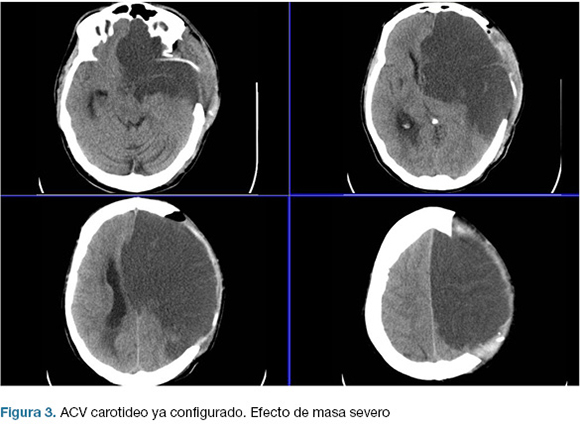

Se realizo una hemicraniectomía decompresiva de emergencia. En el post operatorio ingreso a centro de terapia intensiva (CTI), con intubación orotraqueal (IOT), en asistencia respiratoria mecánica (ARM), sin apertura ocular al llamado, sin gestos, localizando con miembro superior izquierdo; CGS 7. Las cifras de presión intracraneanas (PIC) fueron menores a 20 mmHg en las primeras 24 horas, y luego ascendieron hasta 40 mmHg, instalando midriasis a izquierda. TC de control evidencio infarto configurado de todo el territorio de la arteria carótida interna izquierda (Figura 3).